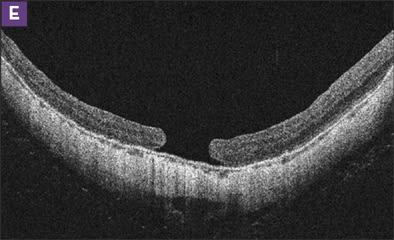

Figure 2. MHRD (A and B) was repaired by vitrectomy with epiretinal membrane removal and C2F6 gas (C). Three months later, the detachment recurred (D). Reoperation with internal limiting membrane peeling and gas repaired the detachment, although the macular hole remained open (E). Visual acuity improved from 20/400 to 20/200.